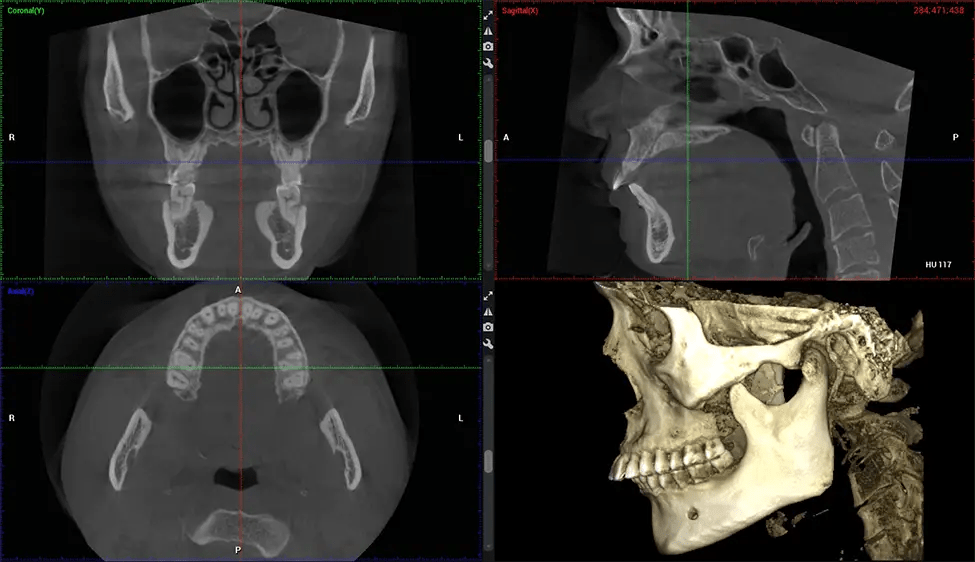

Cone Beam Computed Tomography (CBCT) is an advanced imaging technique used in dentistry and maxillofacial surgery to obtain detailed 3D images of the oral and maxillofacial structures. At Dr G Dental Studio, our CBCT scanners utilize a cone-shaped X-ray beam and a specialized detector to capture images from different angles. A computer then combines these images to create a 3D representation of the patient’s oral anatomy.

This 3D scan, called cone beam computed tomography, gives your dentist a more complete image of your oral anatomy and disease processes than a traditional X-ray. Unlike conventional X-rays, which capture a 2D image of your mouth from various angles, a 3D scan takes multiple digital X-rays for one image. It provides a complete view of your jaw, teeth, nerves, and soft tissues. This enhanced view allows dentists to detect minor issues not visible in traditional 2D scans, such as impacted wisdom teeth or bone fractures in the sinus cavity.

There are many benefits to using CBCT technology, especially compared to the traditional 2D X-ray format. One of the most significant advantages of CBCT scans is that they provide much more information than traditional X-rays. A scan lets your dentist see images from all angles of your jaw and mouth, including your sinuses, nasal cavity, cheekbones, and other surrounding areas. This added information helps your dentist craft a comprehensive treatment plan that addresses all aspects of your oral health.

After the scanning process, the captured X-ray images are processed by the CBCT software, which applies algorithms to reconstruct a detailed 3D image of the scanned area. The software compiles these individual X-ray images and creates a digital 3D representation of the patient’s anatomy. The reconstructed 3D CBCT image can be viewed and analyzed by the dentist or radiologist. This image can be manipulated, rotated, and zoomed in or out to examine specific structures and evaluate the patient’s condition.

Planmeca Viso G7 CBCT ( Cone Beam CT Scan ) is designed to surpass the demands of industry leaders, specialists, and large institutions. It’s has a large ø25×30 cm sensor with four built-in cameras. It can capture unlimited volume sizes from a ø3×3 cm to a ø30x30cm volume capturing the skullcap through C7 on the cervical spine. The Planmeca Viso G7 offers the industry’s largest single volume scan of ø30×19 cm. It’s poised to handle advanced imaging modalities such as Planmeca ProFace® and Planmeca 4D™ Jaw Motion technology. The occipital head support allows an unimpeded view of facial tissue.